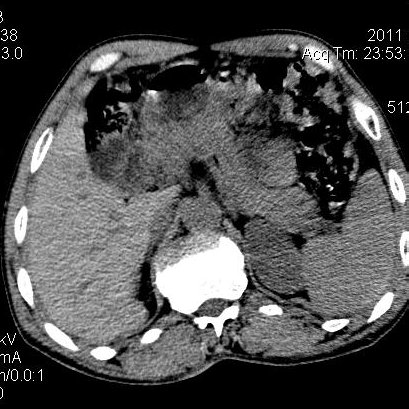

肝左叶发育异常

男性,55岁,骑摩托车摔倒后入院,自述右上腹疼痛

[backcolor=#FF0000]第一次诊断的时候也是这么肯定,可是床旁超声检查并没有发现明显异常,而且患者的一般症状都良好。还好临床只是保守治疗,没有立即手术,第二次复查的时候没有一点变化,又做了MRI检查,没有血肿,

这是一例肝左叶发育异常的,很个性吧~[/backcolor]